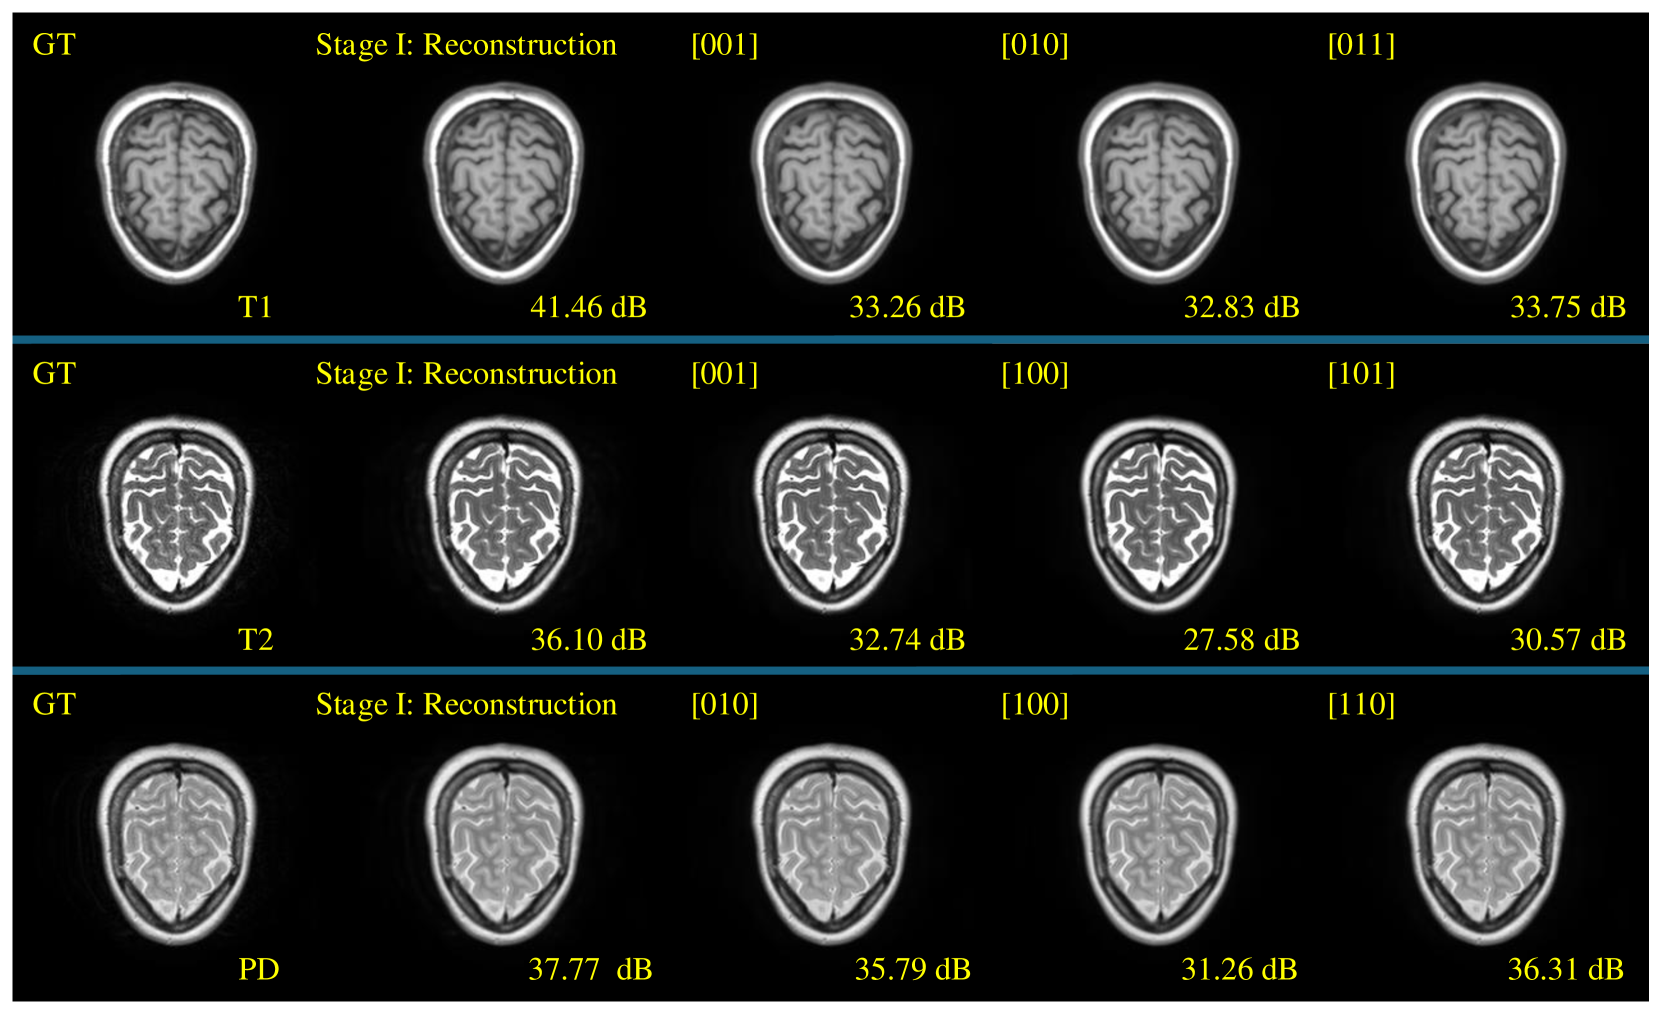

Refer to caption

Figure 3: Exemplar synthesized brain MRI scans of our CodeBrain on the IXI dataset. There are original modalities (1st column), reconstructed results of Stage I (2nd column), and Stage II’s imputed results in different scenarios (3rd/4th/5th columns, respectively).

Table 1 gives quantitative synthesis results in different settings. Overall, PD is easier to synthesize from other modalities and T2 contains more hard-to-restore details, indicating the importance of T2 examinations in clinical practice. Furthermore, different one-to-one imputation results (i.e., the top of Table 1) show that T1 can be better transformed from PD than T2, while T2 and PD are highly related, as stated in [27, 29]. Fig. 3 further shows brain MRI imputation results in different scenarios on the IXI dataset. We can see that: 1) The Stage I of our CodeBrain model captures most target details for reconstruction (i.e., the 2nd column in Fig. 3); 2) Our Stage II model generates accurate and plausible anatomic structures for different missing modalities in different scenarios for brain MRI.